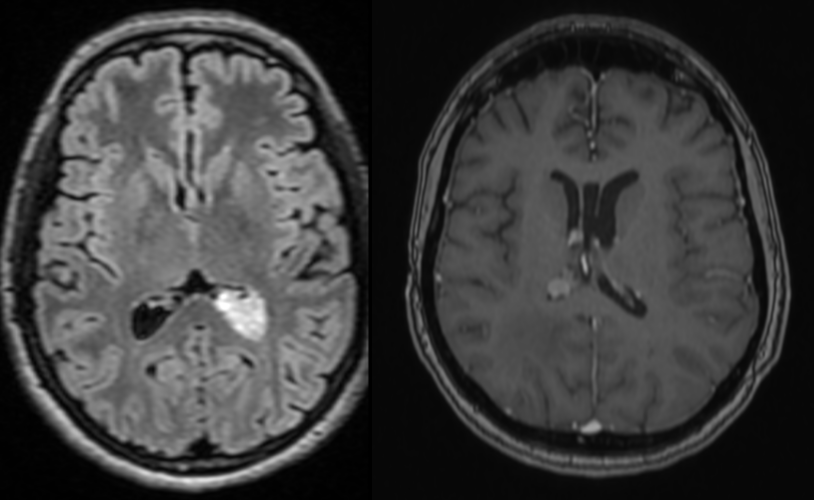

– Investigații imagistice: RMN (rezonanță magnetică) și/sau CT (tomografie computerizată), care evidențiază masa tumorală și hidrocefalia asociată

Simptomele sunt cauzate de obstrucția fluxului normal al lichidului cefalorahidian, ceea ce duce la hidrocefalie (acumulare excesivă de lichid în creier). Când se dezvoltă în ventriculii laterali pot determina simptome datorate hipertensiunii intracraniene și afectării circuitelor neuronale locale (deficite neurologice focale).